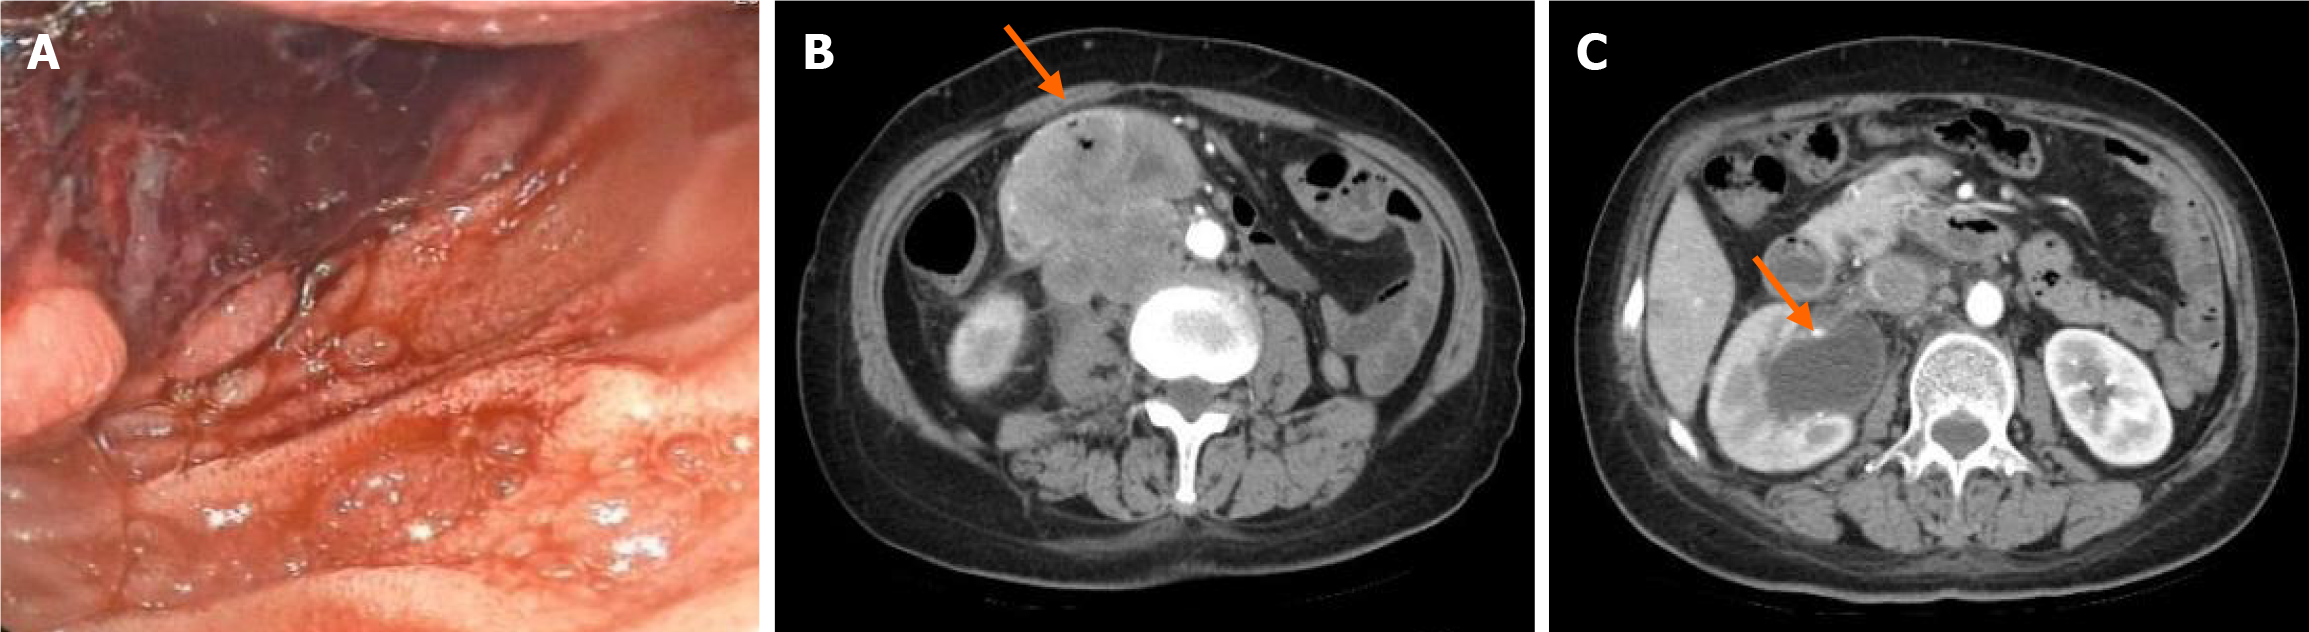

Figure 2 After receiving chemotherapy, immediately before pembrolizumab.

A: Upper gastrointestinal endoscopy showed a mass in the descending duodenum with numerous violaceous necrotic tissue and blood clots on the surface; B: Computed tomography (CT) showed a duodenal mass with possible retroperitoneal lymph node metastasis; C: CT showed dilated right renal pelvis and abdominal ureter.